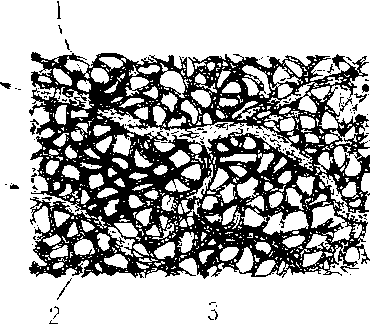

蛙足蹼内的微管网

1.小静脉 2.小动脉 3. 吻合(交通支)